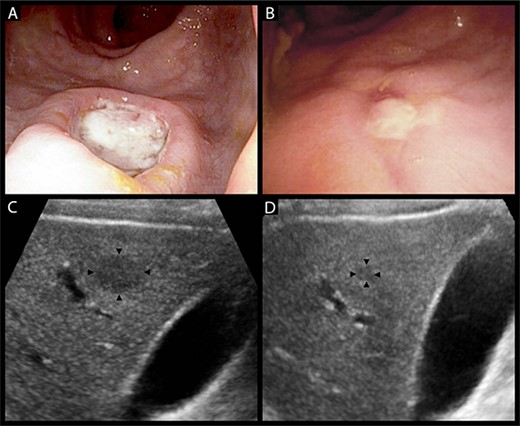

An inpatient colonoscopy demonstrated a 2-cm ulcer with heaped margins and a necrotic base in the lower rectum that was biopsied with endoscopic forceps (Fig. 2A). A liver ultrasound was performed for further characterization of the liver lesions (Fig. 2C). The patient was discharged with resolution of his acute symptoms, for ongoing close follow-up as an outpatient. Histopathology of the rectal lesion returned as ulceration with chronic inflammation and atypical crypt epithelium, with no evident neoplastic change on immunostaining. An early interval elective colonoscopy was attended at which time the rectal ulcer had almost entirely resolved (Fig. 2B). Concurrent gastroscopy at this time was unremarkable. The patient was referred for a CT-guided liver biopsy, with a finding of scattered granulomas with extensive areas of necrosis. There were no observed neoplastic cells or microorganisms.

(A) heaped ulcer with a necrotic base in the lower rectum seen on colonoscopy, representing a syphilitic chancre. (B) The same lesion resolving on interval colonoscopy 4 weeks later, prior to the commencement of treatment for syphilis. (C) Hypoechoic liver lesion in segment 6 measuring 19 by 14 mm. (D) The same lesion has decreased to 6 by 5 mm at 6 weeks post-treatment.